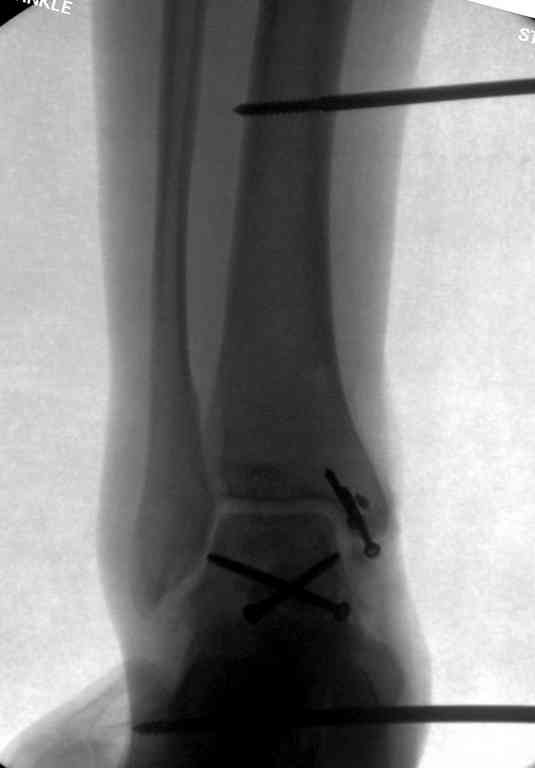

Здесь на фото примеры:

Переломовывих тарана с повреждением медиальной стороны. Через 4 часа после поступления проведена репозиция и фиксация тарана после Irrigation&Debridment. Частичное несращение медиальной лодыжки не беспокоит, вернулся к активному образу жизни. Полная нагрузка разрешена через 11 недель. Финальные снимки через 11 месяцев.